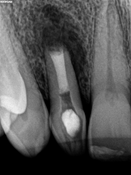

Perfurações dentarias são complicações no tratamento de canal que na maioria dos casos resulta em um prognóstico desfavorável, pois permite a entrada de microrganismos nos tecidos que envolvem o dente. Em alguns casos, devido ao seu difícil diagnóstico, acesso limitado, tempo decorrido ou tamanho da perfuração resultará em um desafio para o profissional conseguir um selamento adequado da área, sendo muito importante o conhecimento sobre o material que será empregado.